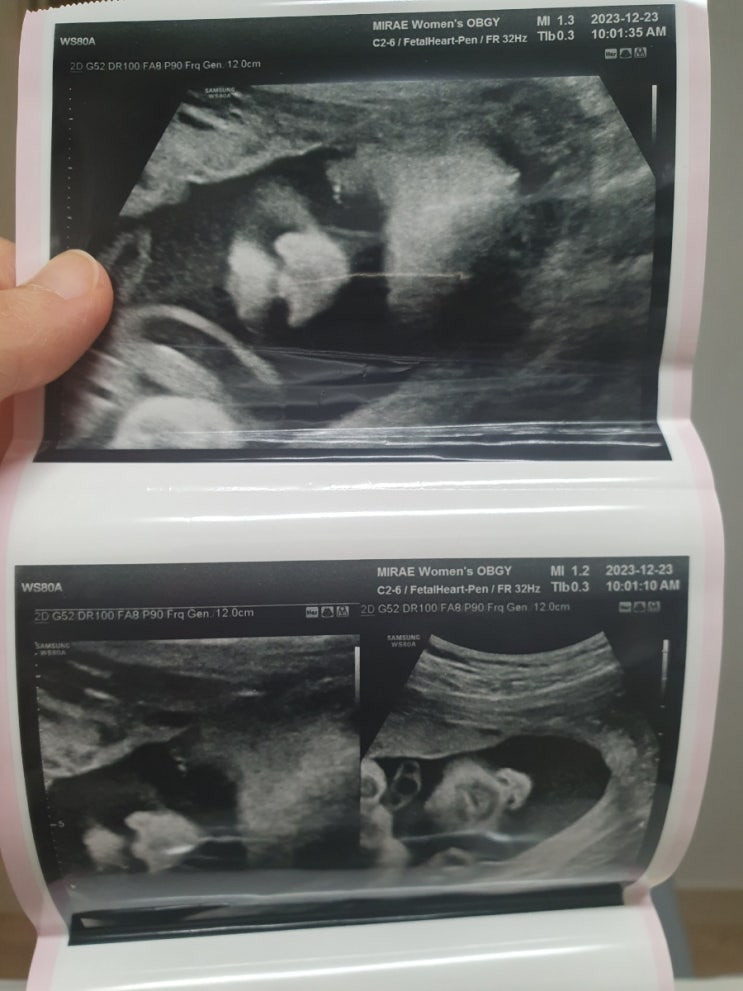

2023년 12월 23일 토요일-31주 1일째 12월 9일 병원가고 이제 부터는 2주뒤에 오래서 2주뒤 병원간날. 오늘...